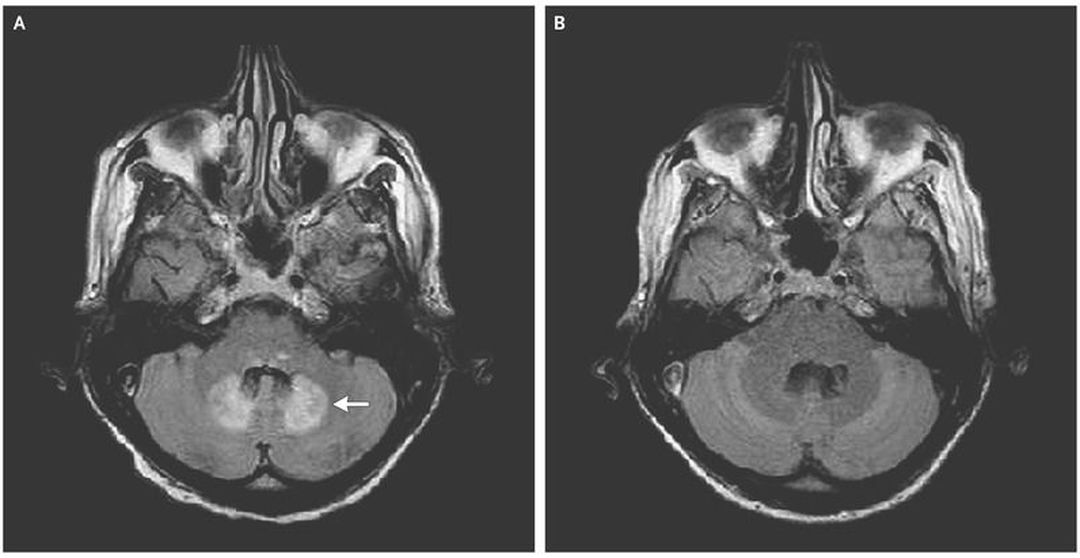

A 58-year-old man with cryptogenic cirrhosis was admitted to the intensive care unit with confusion after a fall at home. He had been taking a prolonged course of metronidazole (500 mg three times per day for >3 weeks) for Clostridium difficile infection. A few days before his hospitalization, dysarthria and gait instability had developed, which had contributed to the fall. A magnetic resonance imaging (MRI) scan of the brain showed a symmetric, enhanced fluid-attenuated inversion recovery (FLAIR) signal in the dentate nuclei of the cerebellum (Panel A, arrow), a finding that is consistent with encephalopathy associated with metronidazole use. On admission, the patient was intubated for airway protection and was sedated; central catheter–related bacteremia developed soon thereafter. Discontinuation of metronidazole resulted in resolution of the imaging findings 1 month later (Panel B). Neurologic assessment was difficult, and the patient never regained his baseline mental status. Encephalopathy associated with metronidazole use is an uncommon side effect of the medication. It typically manifests as dysarthria and gait instability. Risk factors include liver dysfunction and a prolonged course of metronidazole (typical cumulative dose, >20 g). MRI of the brain is usually diagnostic and typically reveals a symmetric, enhanced FLAIR signal in the dentate nuclei of the cerebellum. During the course of hospitalization, this patient died from complications due to central catheter–related bacteremia.